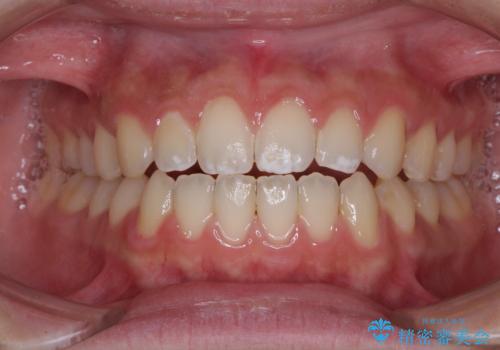

[ 前歯開咬 ] 前歯が噛んでいない マウスピース矯正治療

担当医 大元洋佑